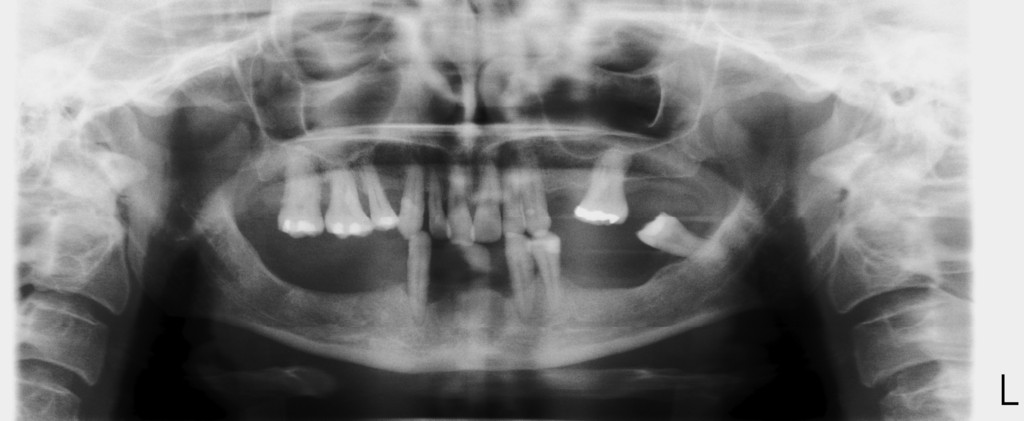

REHABILITACIÓN CON IMPLANTES Y CIRUGÍA PLASTICA PERIODONTAL.

REHABILITACIÓN CON IMPLANTES SIN CIRUGÍA.

REHABILITACIÓN CON IMPLANTES ,ENFERMEDAD PERIODONTAL AVANZADA.

REHABILITACIÓN IMPLANTOSORTADA EN MANDÍBULA Y MAXILAR.

REHABILITACIÓN ESTÉTICA CON IMPLANTES.

• ESTUDIOS   Y PLANIFICACION EN 3D.

•  IMPLANTÓLOGIA  POR ORDENADOR.